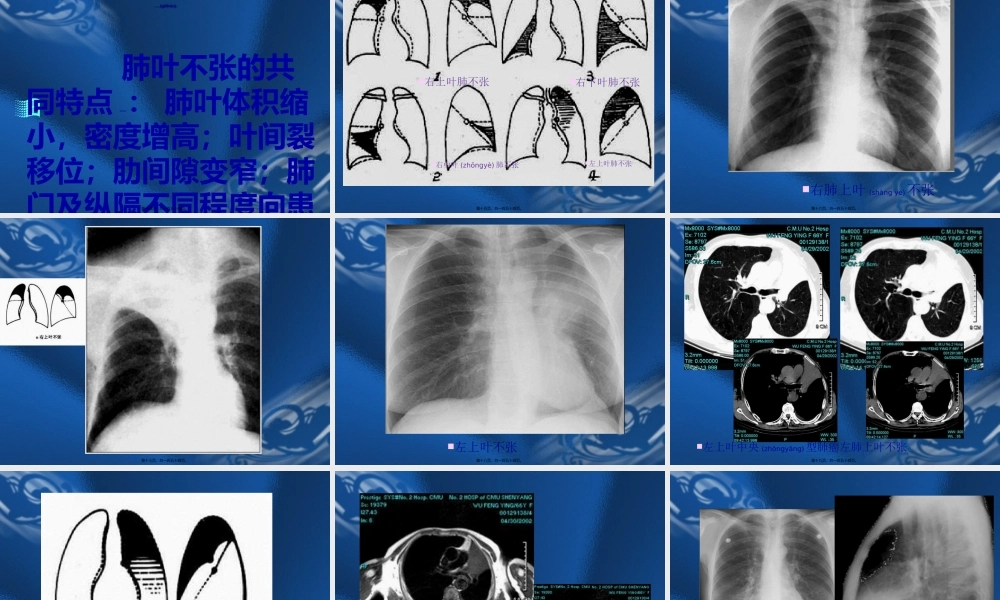

呼吸系统(hūxīxìtǒn)ɡ基本病变的影像学表现天铁集团放射(fàngshè)中心王献忠第一页,共一百五十四页。第一节支气管阻塞性改变(gǎibiàn)第二节肺部改变第三节肺门的改变第四节胸膜病变第五节纵隔的改变第六节膈的改变第二页,共一百五十四页。第一节第一节支气管阻塞性改变支气管阻塞性改变(gǎibiàn)(gǎibiàn)腔内性:肿瘤、异物、炎症、结核、先天性狭窄(xiázhǎi)。腔外性:淋巴结增大压迫。第三页,共一百五十四页。第一节第一节支气管阻塞性改变支气管阻塞性改变(gǎibiàn)(gǎibiàn)一、阻塞型肺气肿(obstructiveemphysema)1、两肺阻塞性肺气肿:见于慢支及支气管哮喘。影像表现:肺野透过度增加,与呼吸(hūxī)时相关系不大;肺纹理稀疏变细,可见肺大泡。横膈低平,活动度减低;胸廓呈桶状,肋间隙增宽;心影狭长呈垂位心型,心后间隙增宽。第四页,共一百五十四页。第一节第一节支气管阻塞性改变支气管阻塞性改变(gǎibiàn)(gǎibiàn)2、局限性阻塞性肺气肿一侧性肺气肿:一叶性肺气肿:影像表现:肺内表现同上;纵隔向健侧移位或移位不明显。气管内异物(yìwù)可表现为纵隔摆动。支气管断层或造影有利于诊断。第五页,共一百五十四页。第六页,共一百五十四页。第七页,共一百五十四页。肺泡(fèipào)肺泡(fèipào)壁终末细支气管第八页,共一百五十四页。小叶(xiǎoyè)中心型肺气肿全小叶(xiǎoyè)型肺气肿第九页,共一百五十四页。肺纹理(wénlǐ)减少、横膈变平、桶状胸、心影狭长。第十页,共一百五十四页。阻塞性细支气管炎(zhīqìɡuǎnyán)(BronchiolitisObliterans)指细支气管发炎的病变(bìngbiàn),导致支气管壁纤维化以及管腔阻塞。第十一页,共一百五十四页。阻塞性细支气管炎(zhīqìɡuǎnyán)(BronchiolitisObliterans)呈现—马赛克灌注,磨玻璃(bōlí)密度区肺血管增粗。支扩肺血管(xuèguǎn)增粗第十二页,共一百五十四页。第一节第一节支气管阻塞性改变支气管阻塞性改变(gǎibiàn)(gǎibiàn)二、阻塞性肺不张(obstructiveatelectasis)1、一侧性肺不张:一侧主支气管完全性阻塞的后果(hòuguǒ)。影像表现:患侧肺野均匀一致密度增高影;胸廓塌陷,肋间隙变窄;纵隔向患侧移位;患侧膈肌升高;健侧代偿性肺气肿。第十三页,共一百五十四页。第一节第一节支气管阻塞性改变支气管阻塞性改变(gǎibiàn)(gǎibiàn)肺叶不张...